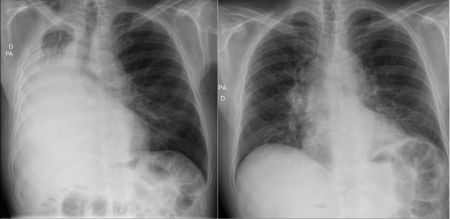

Cazul de fata este al unui pacient de 76 de ani, diagnosticat recent cu un carcinom pulmonar cu celule mici, adus la camera de garda cu insuficiență respiratorie acută. Radiografia toracică evidenția atelectazie masivă a plămânului drept — o situație critică, cu risc vital imediat. Am decis inițierea promptă a chimioterapiei. La 72 de ore, controlul radiologic a arătat reexpansiune pulmonară semnificativă, cu ameliorare clinică evidentă. O intervenție rapidă, corect indicată, a transformat o urgență majoră într-o situație stabilizată.